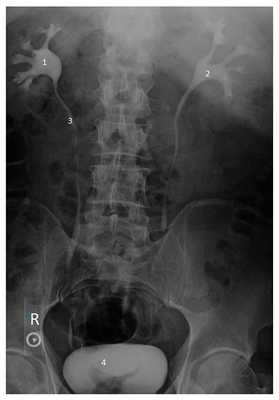

Рентгеноконтрастные исследования мочевыделительной системы

Рентгенологические методы с использованием контрастных веществ основаны на использовании рентгенологических лучей и специальных веществ, способных к поглощению их поглощению. Контрастное вещество вводится в организм, и когда оно попадает в мочевыделительную систему, выполняется серия рентгенологических снимков, позволяющих оценить анатомическое строение почек, мочеточников, мочевого пузыря, определить степень гидронефроза и уровень нарушения оттока мочи. Наиболее широко применяются методы микционной цистоуретрографии и экскреторной или внутривенной урографии. Они являются достаточно информативными. Недостатком является необходимость использования контрастных веществ для визуализации мочевыделительной системы почки, что может быть ассоциировано с развитием аллергических реакций и нарушением работы почек.

Рисунок. Экскреторная урография. 1 и 2 - чашечно-лоханочная система правой и левой почки, 3 - мочеточник, 4 - мочевой пузырь.